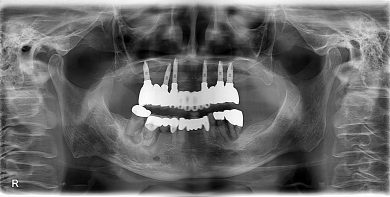

インプラント症例 術後18年 上顎無歯顎 オペ時72歳 現在90歳 上顎オールオン6

パノラマレントゲンから、上の歯は前歯6本、右上小臼歯1本残存してますが、動揺度は2~3度。ほぼ3度。左上の部分床義歯は不安定でした。

18年前ですので、サージカルガイドの精度はイマイチで、右上の臼歯部は造骨処置(いわゆるサイナスリフト)を行いました。

インプラント6本 サイナスリフト2ヵ所 オールオン6 仮歯 総費用約350万

18年後の補綴。クラシカルですが、十分機能しています。

歯科医師ならではの“あるある”ですが、名前では思い出せなくても、レントゲンを見れば当時の治療の記憶が一瞬で蘇ることがあります。

18年前に埋入したインプラントの形、位置、周囲の骨の状態を見た瞬間に、当時のオペ室の空気感まで思い出したのです。